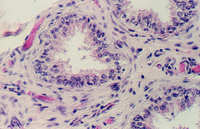

Look at slides 5 and 72 for sections through the epididymus. The first set of tubules you need to find, however are the EFFERENT DUCTULES. These are lined with a low pseudostratified epithelium that is very ragged. Sometimes the tubules look "festooned". The efferent ductules receive sperm from the Rete testes channels. Then they merge to form the single duct of the EPIDIDYMUS. Consult an overview showing the organization of the male reproductive system. Efferent ductules are shown in the following photos.

This low magnification shows the ragged, festooned appearance of the Efferent ducts.

The low pseudostratified epithelium is shown in the following photos.

As the Efferent ductules merge, the epithelium gradually changes to simple columnar with tufts of STEREOCILIA. The following photograph shows a higher efferent ductule on the right and an epididymal duct on the left.